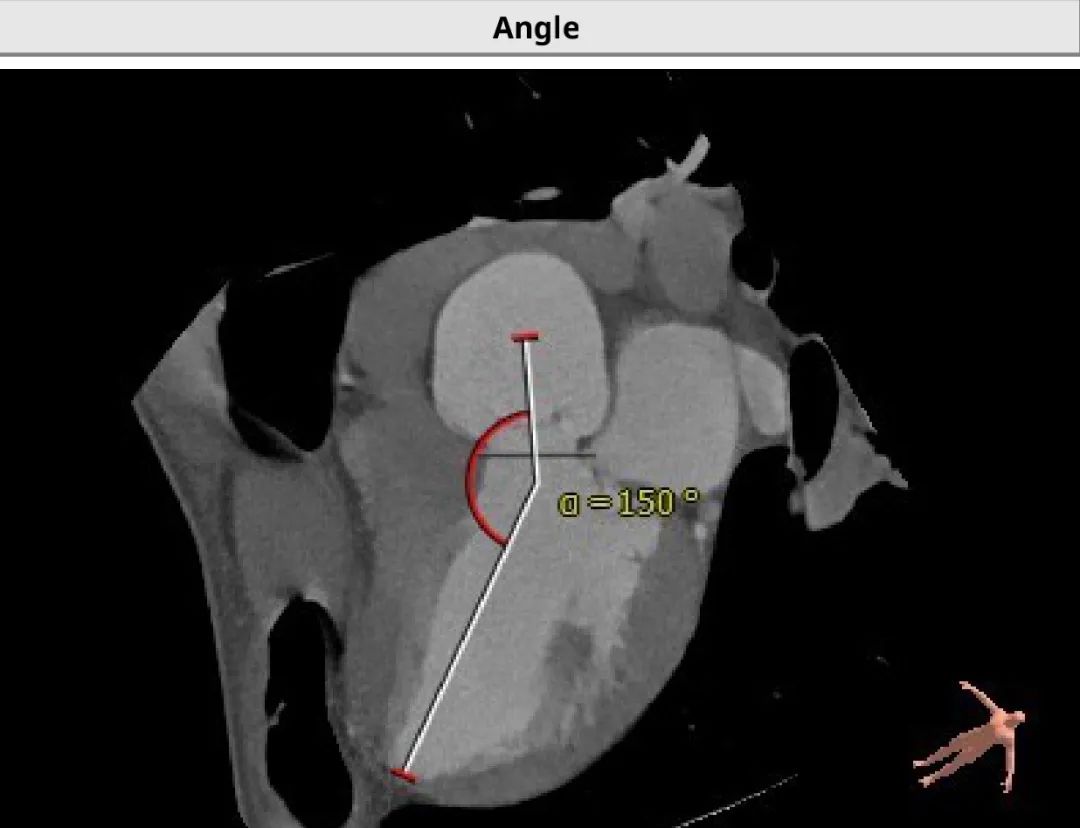

4.患者术中造影角度RAO:11°,CAU:16°。

患者术中最佳投射角度